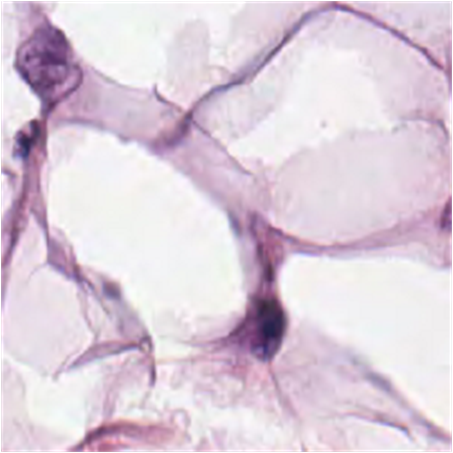

(f) CHMNIST dataset

[Uncaptioned image]

Generalization from Base-to-Novel Classes

In our evaluation, we compared the proposed method against several state-of-the-art techniques, including zero-shot CLIP, and prompt learning methods like CoOp, CoCoOp, and MaPLe, thus establishing a robust benchmark for performance assessment. As depicted in Table 7(h), our method outperforms all others in all the medical image recognition datasets. For the base categories, our method demonstrates a remarkable 1.66%percent\% performance improvement. Additionally, when it comes to the novel categories, our method achieves an even more impressive 4.35%percent\% performance improvement. In terms of the harmonic mean, our method elevates the performance from the second-best at 49.45%percent\% to an outstanding 53.08%percent\%. Specifically, our approach excels in the BTMRI dataset, achieving over 3%percent\% performance improvement across all categories. Notably, it achieves a remarkable 5.53%percent\% performance improvement specifically for the novel categories. While our method may not achieve the top performance in terms of novel categories in the CHMNIST dataset, it does obtain the best performance among all prompt-learning methods. Moreover, our method continues to dominate when considering the overall performance evaluation metric, HM. Similar encouraging results are observed in the CCBTM dataset. For the base categories, our method obtains the best performance compared to all prompt-learning methods. Furthermore, the harmonic mean shows a 1.52%percent\% performance gain, further highlighting the strength and effectiveness of our proposed approach.